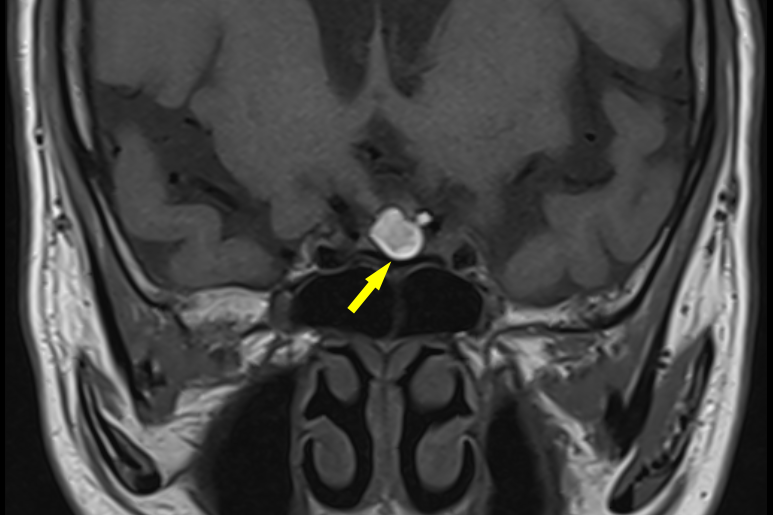

结合这些表现,特别是检验报告中不寻常的各项激素指标下降,都共同指向这些内分泌激素的司令部—脑垂体,所以,我们将此作为重大‘嫌疑’,立即做了头颅核磁共振(MRI)。赵主任很为内分泌团队敏锐的观察能力和清晰的临床思路骄傲,果不其然,一枚瘤体赫然出现在了MRI影像中(图3),1.1*0.7cm的块头把脑垂体卡得死死的,凶手终于找到了,原来是脑垂体长期受到肿瘤压迫而萎缩,久而久之导致垂体功能减退,脑垂体这个司令部偷懒了,它所控制的内分泌腺体如性腺、甲状腺和肾上腺也跟着一起罢工,分别引起继发性性腺功能减退、继发性甲状腺功能减退、继发性肾上腺皮质功能减退,性腺功能减退会引起雄激素水平明显降低,出现腋毛、阴毛脱落和肌肉萎缩、肌无力等症状。甲状腺功能减退引起怕冷、乏力、声音嘶哑、记忆减退和情绪低落等,很容易被误诊为抑郁症。肾上腺皮质功能减退可引起乏力、食欲减退甚至恶心、呕吐,严重者引起低血糖、低血压甚至昏迷。

图3. 垂体核磁共振(MRI)显示垂体瘤向鞍上生长(箭头所示)

进一步进行眼科检查时还发现,龚叔叔已经有部分视野缺损,这是由于脑垂体肿瘤往上生长压迫视神经所致,正常人轻轻松松视觉扫描到的区域,在龚叔叔身上已经打了折,对日常生活造成了不少困扰。严重时会引起失明,如果肿瘤往下长,会顶破颅底导致脑脊液鼻漏。如果向两侧发展会压迫海绵窦,海绵窦里面有许多颅神经,比如压迫面神经就会引起面瘫,压迫动眼神经,会引起眼睛运动障碍等等。解除这些压迫症状,需要及时的手术治疗。赵主任指着肿瘤解释到。